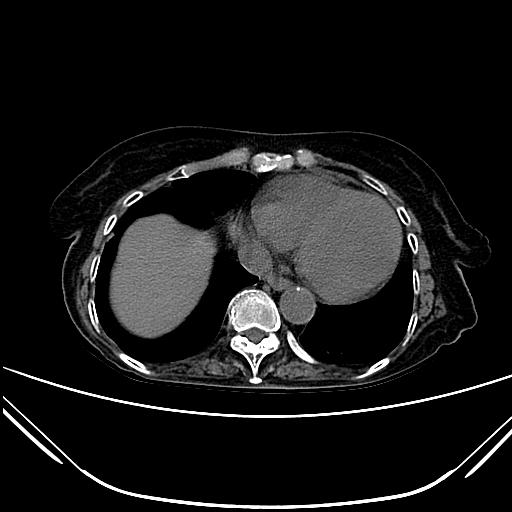

CT51127:胸部CT会诊28243

患者:女,74Y,咳嗽1个月,双肺呼吸音粗。求教右肺下叶背段结节病灶性质。

两肺见少许条索状影,右下肺见胸膜下结节,建议随防,

两肺见少许索条结节影,结节位于右肺胸膜下,考虑两肺少许炎症,右下肺结节,建议随访。